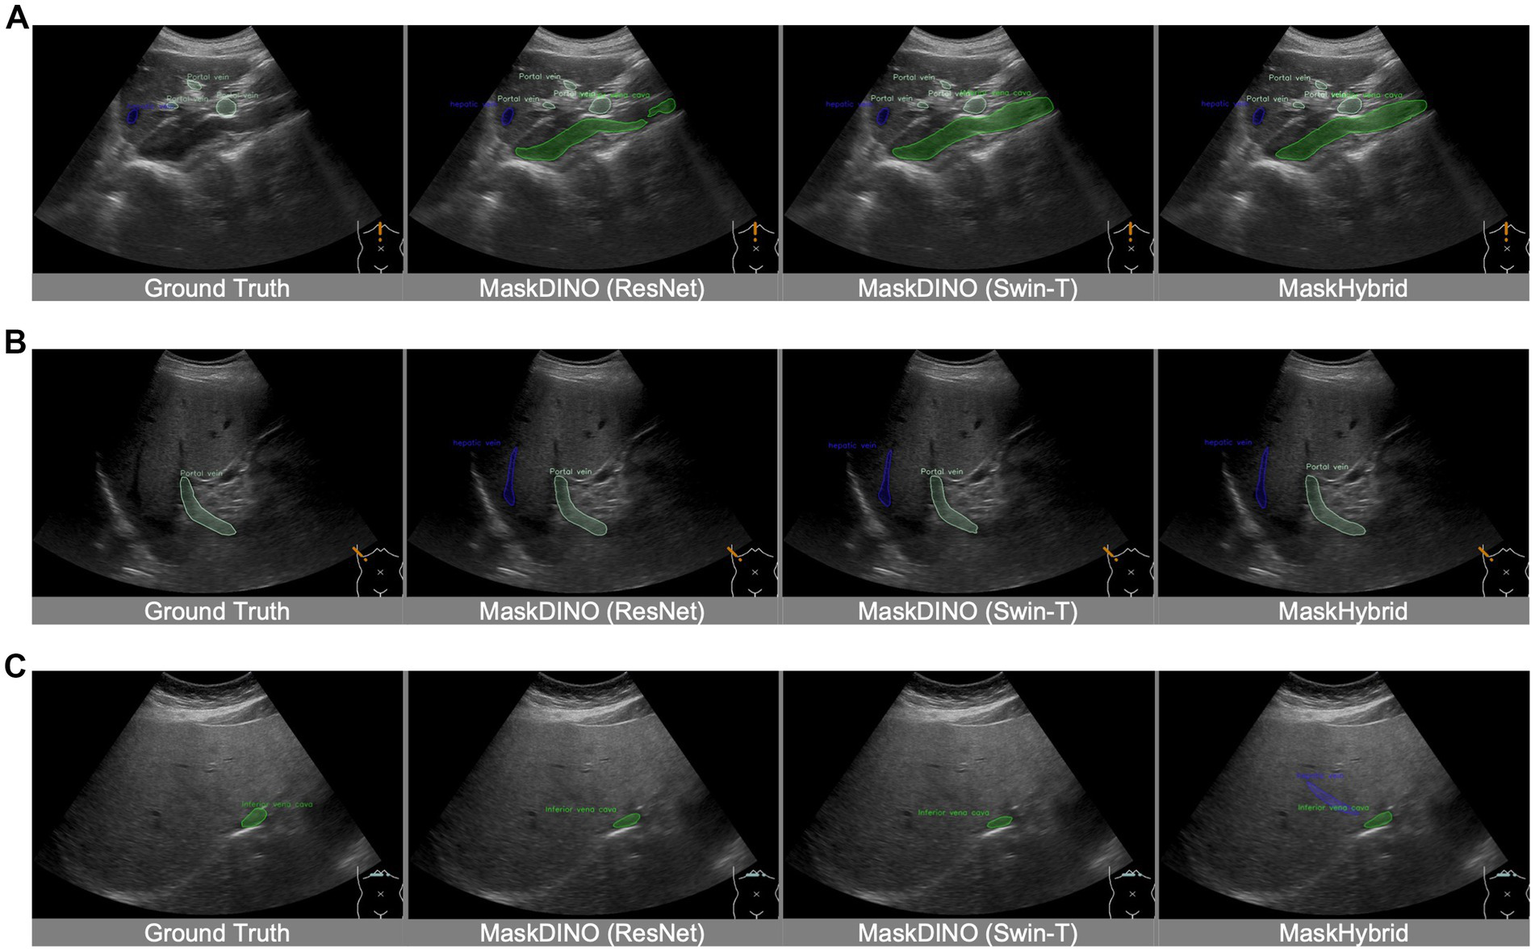

Additionally, incorporating the MaskHybrid encoder enhanced visual interpretation in some clinical scenarios while still maintaining similar competitive performance, validating the effectiveness of this novel approach. For instance, while candidate models approximated the location of anatomical structures, only the MaskHybrid with hybrid encoder correctly identified the hepatic vein in Figure 5A and showed a more comprehensive tumor distribution than MaskDINO (Swin-T) and MaskHybrid in Figure 5B.

Figure 5

Visualization comparison of MaskHybrid models with and without the hybrid encoder. Both (A) and (B) are segmentations of hepatic veins and tumors. MaskHybrid with the hybrid encoder correctly identified the hepatic vein in (A) and showed a more comprehensive tumor distribution in (B).